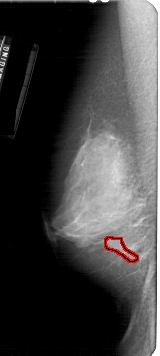

A_1927_1.LEFT_MLO

LEFT_MLO LINES 5326 PIXELS_PER_LINE 2386 BITS_PER_PIXEL 12 RESOLUTION 43.5 OVERLAY

FILE: A_1927_1.LEFT_MLO.OVERLAY

TOTAL_ABNORMALITIES 1

ABNORMALITY 1

LESION_TYPE CALCIFICATION TYPE PLEOMORPHIC DISTRIBUTION CLUSTERED

ASSESSMENT 4

SUBTLETY 2

PATHOLOGY BENIGN

TOTAL_OUTLINES 1

BOUNDARY